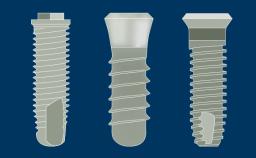

Introduction to Implant Dentistry

Implant Designs and Characteristics

Learning Module